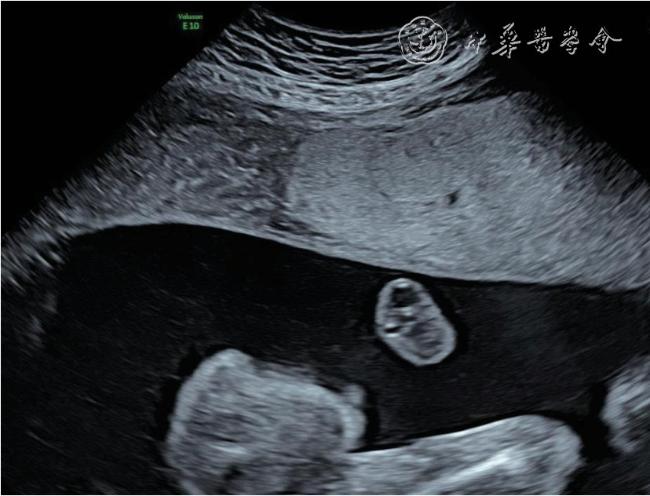

图2 双胎贫血-红细胞增多序列征胎儿孕22+5 周产前超声图像可见供血儿脐带入口附近胎盘回声增强、增厚,受血儿脐带入口附近胎盘回声减低、较供血儿侧薄